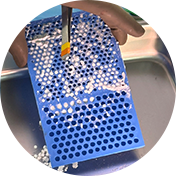

V-pop 프로그램을 이용한

세심한 수술 계획,

수술 중 발생할 수 있는 변수 조절

예은동물의료센터는 V-pop 프로그램을 이용하여 세심한 수술 계획을 세우고 수술 중 발생할 수 있는 변수 조절합니다.

또한 다양한 정형외과 회사 제품 보유로 환자 맞춤 수술 가능합니다.

다양한 크기/다양한 뼈 모양에 가능한 기구 보유하여 리허설을 통해서 환자에게 가장 적합한 플레이트 이용합니다.

Synthes plate vs fixin plate

fixin plate vs jeil medial plate

- 다양한 정형외과 회사 제품 보유로 환자 맞춤 수술 가능

- 다양한 크기/다양한 뼈 모양에 가능한 기구 보유

- 리허설을 통해서 환자에게 가장 적합한 플레이트 이용

보유 회사 제품: Fixin, Jeil Medical, Vi, Synthes